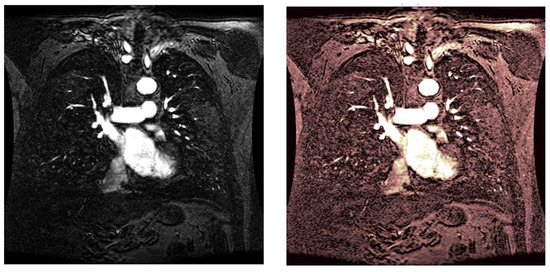

As statistical data have less relevance for life sciences, we add graphical displays of the studied angiograms. Surprisingly, even a simple denoising procedure can help reduce unwanted artifacts, as can be observed when comparing the angiogram E1154S7I064 (shown in Figure 5) with the result obtained by denoising it with the CLAHE method already described (shown in Figure 6). The corresponding image obtained by the wavelet-based CE method (shown in Figure 7) better outlines the biological features, making visible some details that cannot be observed in the original image (Figure 5), and allows us to take into consideration relinquishing contrast substances (a fact with multiple benefits for newborns and children). A visual comparison of CLAHE and wavelet-based CE method results in the performance obtained for this angiogram can be made with the images in Figure 8. It can be noticed that the original image is too dark to observe all the significant medical details and that the result of CLAHE is too luminous and can mask medical features. The same remarks concerning the advantages of the wavelet-based CE methods can be made upon a visual analysis of the original angiograms and the corresponding results shown in Figure 9, Figure 10, Figure 11 and Figure 12.

Figure 10. Original angiogram E1154S7I026 (left) and wavelet-based CE method result (right).

Figure 11. Original angiogram E1154S7I053 (left) and wavelet-based CE method result (right).